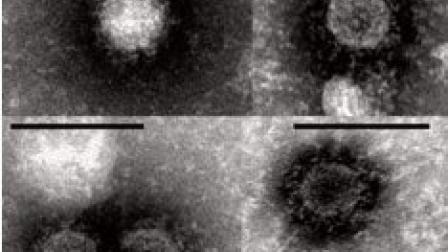

CIUDAD DE MÉXICO, 26 de junio.- México registró en Jalisco el primer caso del virus de Chikungunya, el cual es transmitido por la picadura de mosquitos Aedes Aegypti y Aedes Albopictus, logrando detectarse entre tres y siete días después.

La enfermedad, que principalmente se presentó en África, Asia e India, se reportó por vez primera en Europa en el 2007. Mientras que en 2013, se registraron los primeros casos en América, de acuerdo a la Organización Panamericana de la Salud.